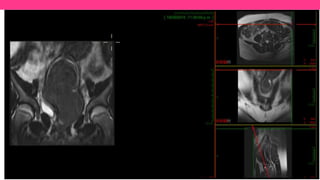

Fig. 4: Fig. 4: Síndrome de Mayer-Rokitansky-Küster-Hauser. A . Sagital FSE T2. B y C. Axial FSE T2. D. FSE T2

con supresión de grasa . La RM muestra la ausencia de útero y vagina. La uretra (flecha blanca sólida) está

situada inmediatamente anterior a la pared rectal (flecha blanca transparente). Agenesia renal izquierda (triángulo

blanco sólido).

Fig. 4: Fig.4: Síndrome de Mayer-Rokitansky-Küster-Hauser. A . Sagital FSE T2. B y C. Axial FSE T2. D. FSE T2 con supresión de grasa . La RM muestra la ausencia de útero y vagina. La uretra (flecha blanca sólida) está situada inmediatamente anterior a la pared rectal (flecha blanca transparente). Agenesia renal izquierda (triángulo blanco sólido).